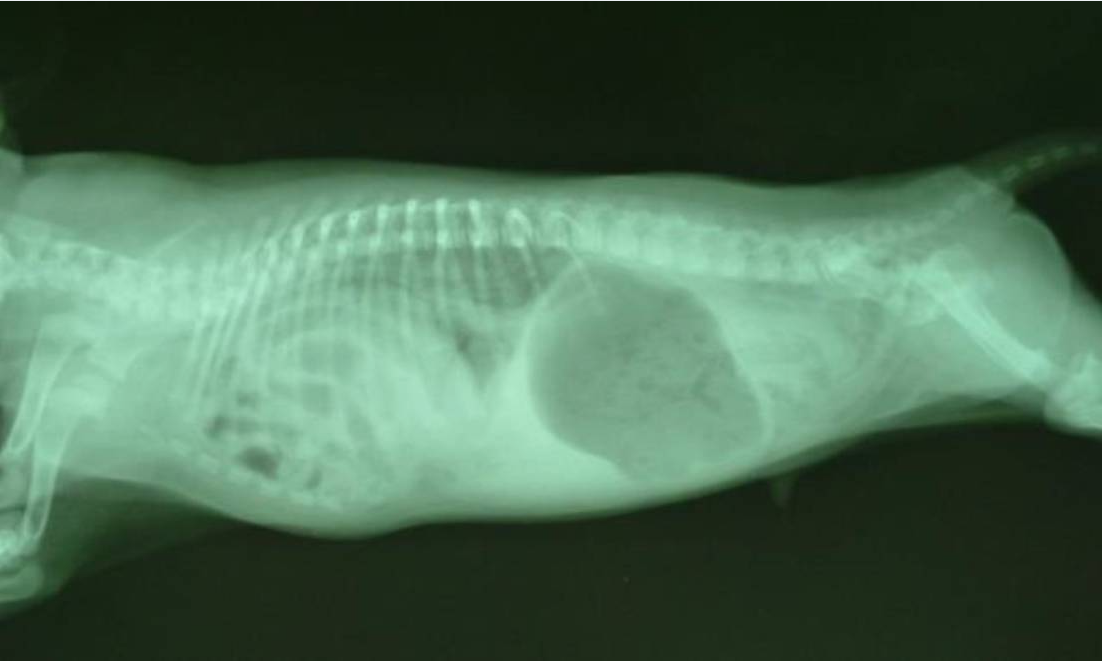

Peritoneopericardial Diaphragmatic Hernia (PPDH)

PPDH is the most common congenital pericardial defect in dogs and cats. It results from incomplete development of the septum transversum, creating a communication between the pericardial and peritoneal cavities.

Key Features

- Breed predisposition: Weimaraners (may be inherited)

- Commonly herniated organs: Liver (most common), small intestine, omentum, spleen, stomach

- Associated defects: Umbilical hernia, sternal malformations, VSD

- Clinical signs: Often incidental finding; may have GI signs (vomiting, anorexia) or respiratory signs

- Diagnosis: Radiography (gas/soft tissue over heart), echocardiography, contrast studies

- Treatment: Surgical correction if symptomatic; asymptomatic cases may be monitored

Figure 6 - Lateral thoracic radiograph of a dog with PPDH showing gas-filled bowel loops overlying the cardiac silhouette and loss of the diaphragmatic line